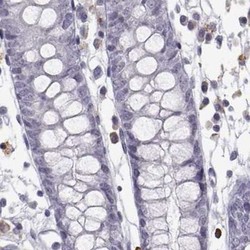

- Immunohistochemistry-Paraffin: VGF Antibody [NBP2-31596] - Staining of human colon.